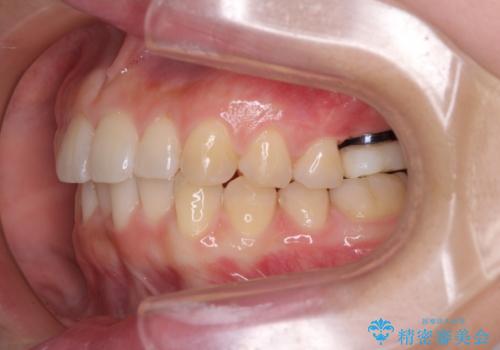

インプラントによる補綴治療とインビザライン矯正

- 抜歯が必要と診断された奥歯を気にして来院された患者様です。

抜歯の上インプラントによる補綴治療を行うこととなりましたが、前歯の叢生も気になるとのことで並行して矯正治療を行うこととしました。

歯列不正は軽微であったので、インビザラインによる矯正治療とし、矯正治療中にインプラント埋入を行う予定としました。

痛みがないので、ボロボロのまま放置していましたが、抜歯後は汚れが溜まりにくくなりスッキリとしたようです。

前歯のデコボコも解消され、ブラッシングが楽になりました。